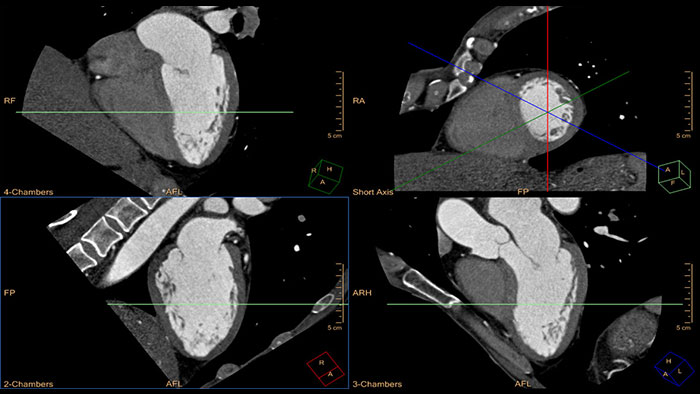

Kompleksowa analiza badań CT serca

Ta aplikacja pozwala na automatyczną segmentację całego serca w oparciu o model trójwymiarowy, jak również segmentację tętnic wieńcowych bez udziału użytkownika, umożliwiając automatyczną ekstrakcję i wizualizację całego drzewa naczyń wieńcowych.

– map kodowanych kolorem w projekcjach w osi krótkiej, – map segmentacji w projekcjach w osi krótkiej i map biegunowych wyświetlanych razem z obrazami referencyjnymi w projekcjach w osi długiej, – objętościowej wizualizacji tętnic wieńcowych wraz z mapami segmentacji wyświetlanymi jako nakładki na powierzchnię trójwymiarowego modelu serca.